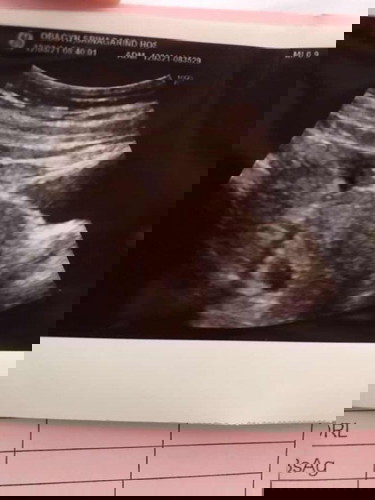

ท้องลม อาการเป็นอย่างไรบ้าง และผลซาวน์นี้เป็นท้องลมไหมคะ

ผลตรวจตั้งครรภ์ ขึ้น 2 ขีด เราเลยนับวัน ปจด มาล่าสุด ได้ 8 W เลยไปตรวจที่ รพ. หมอตรวจและซาวน์ผ่านหน้าท้อง แจ้งว่าพบถุงตั้งครรภ์แต่ไม่พบตัวเด็ก ให้นัดมาซาวน์ใหม่อีก 2W ซึ่งผลซาวน์นี้เหมือนท้องลมไหมคะ เป็นกังวลว่าจะไม่เจอน้องค่ะ😢